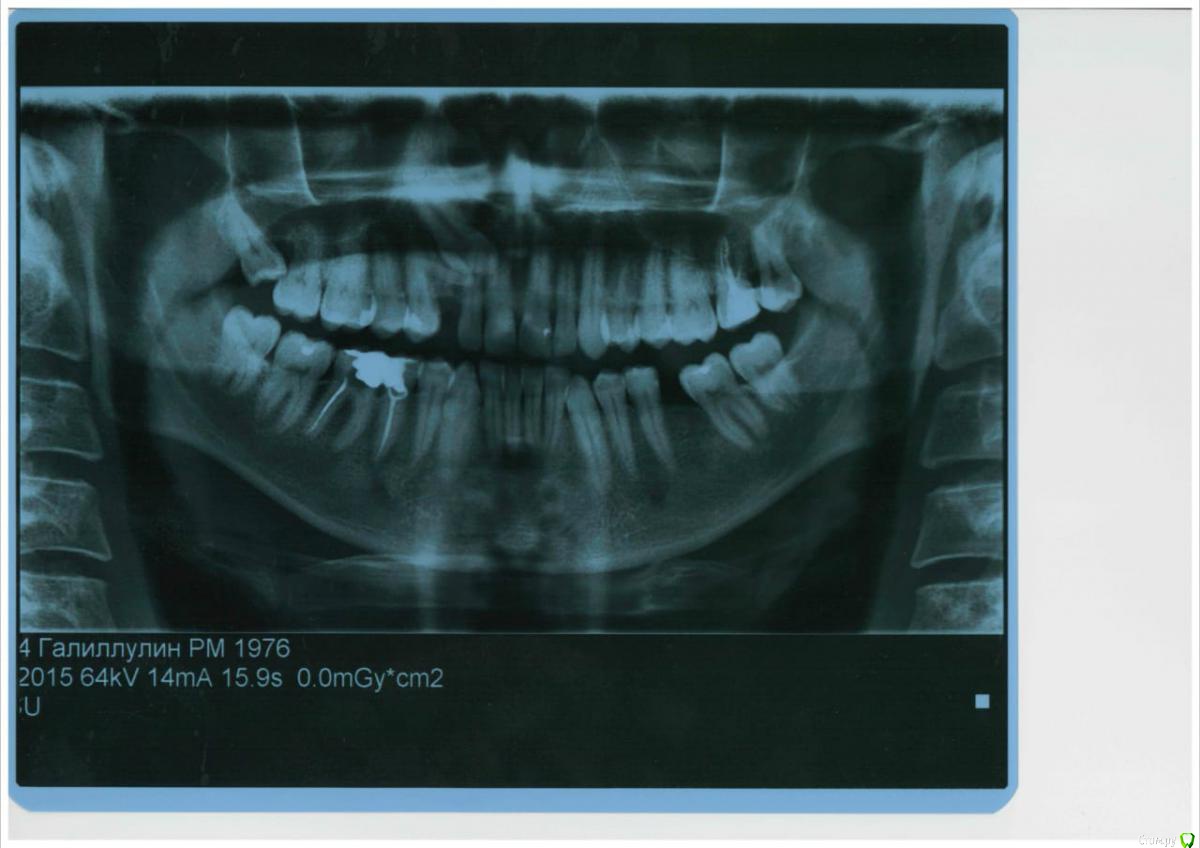

red_butler Опубликовано 7 июня, 2018 Поделиться Опубликовано 7 июня, 2018 Здравствуйте.Имеется леченый зуб, пломбой 20 лет назад. Ортодонт предлагает два пути решения, удалить 6ку и брекетами сдвинуть 7 и 8 зубы. Либо выровнять брекетами зубы на 6-й леченый поставить коронку. Выбор за мной, мне 42 года, зуб залечен обычным резорциненным составом, зуб хрупкий.Мой вопрос, возможно ли в моем возрасте передвинуть 7 и 8 зубы вместе с корнями на место 6-го и 7-го соответственно? Это Ваш снимок? Ссылка на комментарий

red_butler Опубликовано 7 июня, 2018 Поделиться Опубликовано 7 июня, 2018 Мой вопрос, возможно ли в моем возрасте передвинуть 7 и 8 зубы вместе с корнями на место 6-го и 7-го соответственно? не стоит, это увеличит срок ортодонтического лечения, а в финансовом плане сопоставимо с имплантацией.P.s. судьба пятого зуба под большим вопросом. Ссылка на комментарий

Катринaa Опубликовано 7 июня, 2018 Автор Поделиться Опубликовано 7 июня, 2018 Это Ваш снимок?Да Ссылка на комментарий

Катринaa Опубликовано 7 июня, 2018 Автор Поделиться Опубликовано 7 июня, 2018 не стоит, это увеличит срок ортодонтического лечения, а в финансовом плане сопоставимо с имплантацией.P.s. судьба пятого зуба под большим вопросом. 5 ка пролечена современными материалами. Ссылка на комментарий

red_butler Опубликовано 7 июня, 2018 Поделиться Опубликовано 7 июня, 2018 Её пока не трогаем.Если сейчас судьба зуба под вопросом, то очень скоро муж его потеряет... Зуб с такой степенью разрушения подлежит протезированию.Тему можно закрывать? Ссылка на комментарий